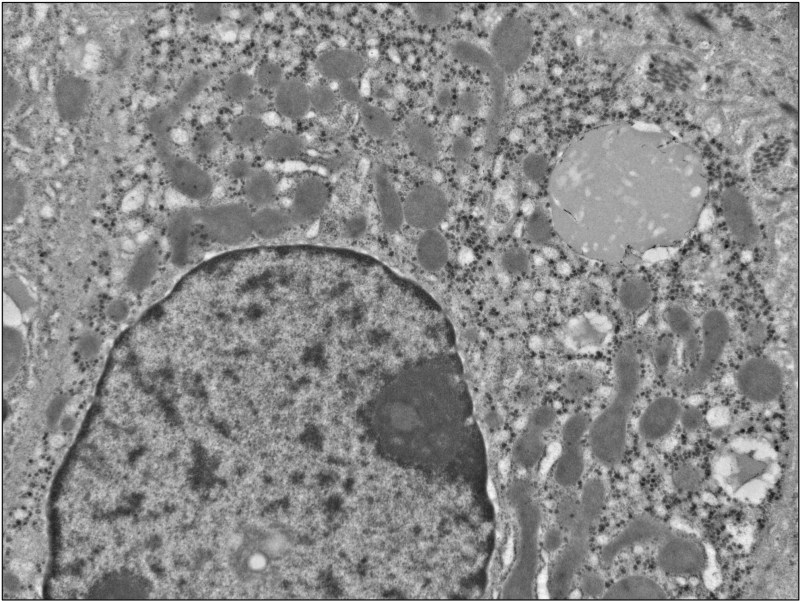

Ultrastructural Findings

- Almost complete loss of peroxisomes with rare questionable small-sized ones

- Scattered bile material

- Scattered micro- and macro-vesicular lipid droplets

- Early trilamellar inclusions (two dark thin linear lines and a line of lucency between them) within the fat droplets

- No other storage materials identified